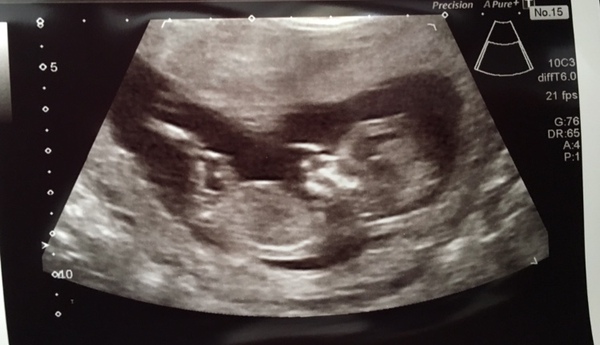

I never shared my scan pic I don’t think it’s a very clear one. What do you think @murphyrocks is there a nub there? I was 13 weeks.

@MisBit1 oh dear if I'm meant to be the nub expert we're in bad shape! πŸ˜‚ As you say it's a bit blurry so hard to tell, possible nub and possibly girl lean but I'm not confident! Anyone else have any thoughts?